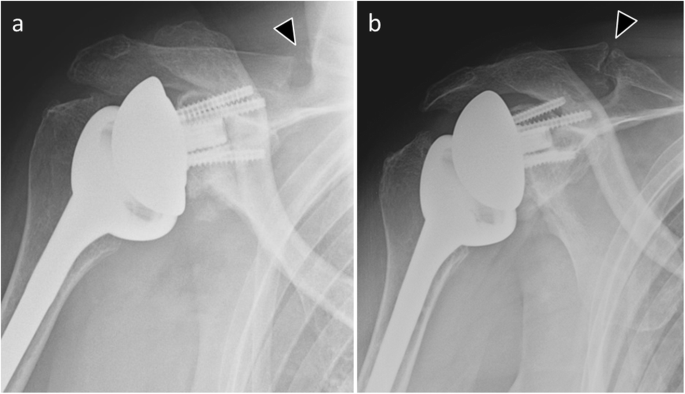

In imaging, ultrasonography helps diagnosis when it directly visualizes the tear [11] (Fig. 19). MRI also contributes to this as long as susceptibility artifacts do not interfere with interpretation. In CT, rupture usually cannot be seen directly because of the hardware artifacts, but a fatty degeneration of the rotator cuff is considered as a reliable indirect sign of a rotator cuff tear (Fig. 20). On standard radiographs, supraspinatus tear is suspected when the distance between the top of the humeral prosthesis and the acromion is less than 5 mm [9]. Anterior translation of the humeral head on anteroposterior and scapular Y views will suggest a subscapularis insufficiency.

Anteroposterior (a) and scapular Y (b) radiographs of a 53-year-old man with total shoulder arthroplasty shows a slight anterior translation of the humeral head (arrow). Transverse grayscale US image (c) of the same patient shows subscapularis tendon rupture (arrowheads) with a retracted tendinous stump (star)